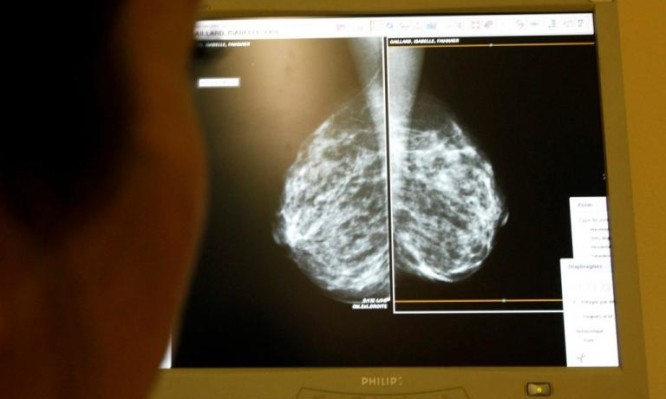

Μ. Βρετανία: 270 γυναίκες θύματα λάθους από το Σύστημα Υγείας – Δεν κάλεσαν 450.000 για μαστογραφία

Ένα "λάθος" φαίνεται να έχει κοστίσει την ζωή σε περίπου 270 γυναίκες στην Βρετανία.

Ένα "λάθος" φαίνεται να έχει κοστίσει την ζωή σε περίπου 270 γυναίκες στην Βρετανία.